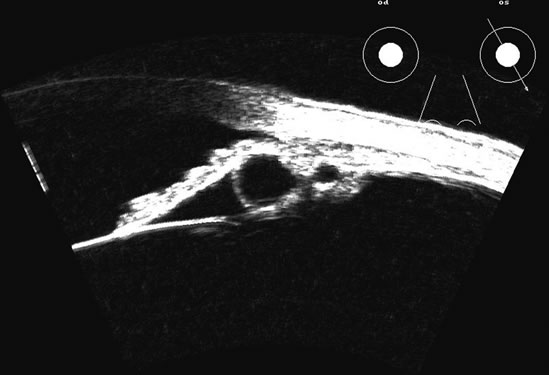

in the 50 MHz range for examining this region.5–7 Lens position, presence, and integrity can be shown most easily with immersion ultrasound, since the proximity of these structures to the transducer in contact techniques makes them difficult to display. Immersion or a water standoff makes it possible to visualize the anterior segment by moving the “noise” of the main bang of the transducer forward, away from the structures of interest and the focal zone onto this area.8 The lens is a “specular” reflector which, like the cornea, is a smooth, highly reflective surface. Whereas specular reflectors, such as the lens, may deflect most acoustic energy away from the transducer when insonified at an oblique angle, “diffuse” reflectors, such as blood-covered membranes, are more easily discerned on B-scan. Blood enhances lens boundaries; that is, it converts the specular reflective surface to a diffuse reflective surface, making the entire outline of the surface more easily seen, even at regions angled so they would otherwise deflect the returning echoes away from the transducer and not be identifiable. The posterior capsule is concave and thus perpendicular to the beam over much of the arc of sector B-scanning, thus making it always easy to identify. The lens outline should be smooth and unbroken (Fig. 1); a damaged lens often is cataractous and has internal echoes as well as interrupted surface echoes.9 Kinetic scanning, that is, real-time scanning while the patient moves his or her eye, can be used to check for mobility of the lens in dislocated or partially dislocated lenses. The four main areas of interest in the posterior chamber to the ocular surgeon are (1) iris and ciliary body tumors, (2) intraocular foreign bodies and trauma that may involve the lens, (3) intraocular lens placement and position that may cause irritation or decreased vision, and (4) hypotony with separation of the ciliary body from the sclera.10 Examples of a retroiridal cyst and a tumor are shown in Figures 2 and 3. Intraocular lens displacement, particularly erosion of haptics that may produce bleeding, is a commonly seen problem. An intraocular lens with a folded haptic is seen in Figure 4 and a retro displaced haptic is shown in Figure 5.